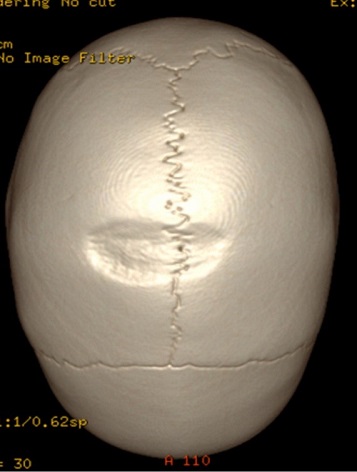

Niña de dos años, sin antecedentes de interés, que en la revisión de los 2 años se aprecia una depresión a nivel del vértex de la calota craneal sin osificación. Se solicita una radiografía de cráneo en la que se observa una depresión radiolúcida en la línea media parietal de la calota, compatible con un foramen parietal (Fig. 1).

Figura 1. Radiografía donde se observa una línea radiolúcida a nivel de la calota